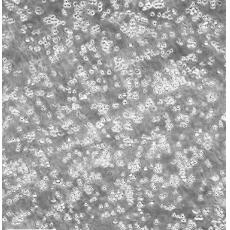

生長(zhǎng)特性 suspension

形態(tài)特征 lymphoblast

細(xì)胞描述 MOLT-4與MOLT-3來源于一名19歲的男性急性淋巴細(xì)胞性白血病的復(fù)發(fā)患者,該患者前期接受過多種藥物聯(lián)合化療。MOLT-4細(xì)胞系為T淋巴細(xì)胞起源,p53基因的第248位密碼子有一個(gè)G→A突變,不表達(dá)p53,不表達(dá)免疫球蛋白或EB病毒;可產(chǎn)生高水平的末端脫氧核糖轉(zhuǎn)移酶;表達(dá)CD1(49%),CD2(35%),CD3A(26%)B(33%)C(34%),CD4(55%),CD5(72%),CD6(22%),CD7(77%)。